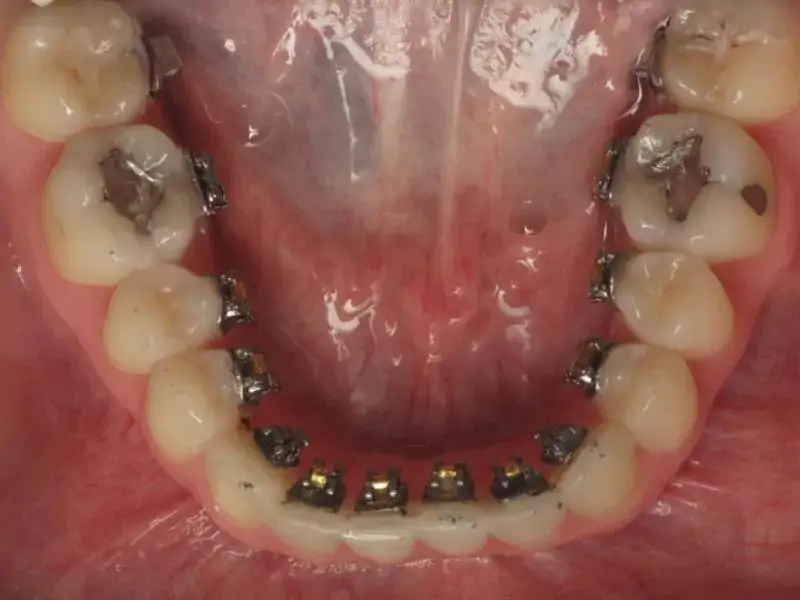

Ortodonti dişlerdeki konum bozukluğunu, çapraşıklığı, ayrıklığı düzelten bir tedavidir. Yapılan müdahale şekillerine göre de ortodonti yani diş teli fiyatlarıfarklılık göstermektedir.

Ortodontik tedaviden sonra dişlerinizde belirgin bir fark olacaktır. Ama düzelen dişleri bozulmadan tutmakta en az ortodonti tedavisi kadar önemlidir. Çünkü ortodonti tedavisi zor bir süreçtir, vakit ayırmanız gerekir, zaman zaman dişlerinizde ağrılar oluşur ve maliyettir. Bu kadar zahmetin altına girip dişlerinizi düzelttirdikten sonra tekrar bozulması canınızı çok sıkacaktır.

Ortodonti tedavisinden sonra dişlerinizin bozulmaması için hem tedavi sırasında hemde tedavi sonrasında alınabilecek önlemler vardır. Diş teli kullanırken ağız ve diş bakımı süreçlerinedikkat etmeniz gerekmektedir. Şimdi bu önlemlerden bazılarını anlatalım;